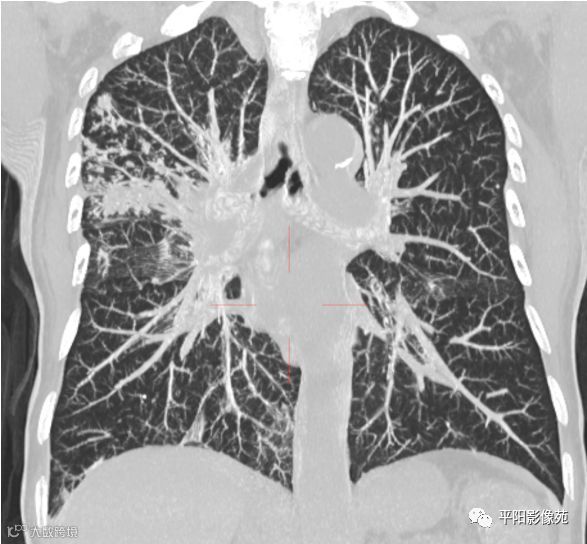

本例影像特点,右主支气管壁肥厚,管腔狭窄不明显,管壁内缘光滑,管腔内有明显病灶堵塞,且远侧各段支气管与其他肺叶表现相同,肺内多发树叶征及实变影。

整体符合渗出、增殖、实变等特点,且病灶形态多样,局部肺间质病变反应较明显,与肺结核特征相符,而肺癌,尤其中央型肺癌,多见于鳞癌,起源于支气管壁,癌灶堆积生长,多会形成肿块且堵塞气管,引起远侧肺组织阻塞性肺气肿、肺炎、肺不张等改变,较晚期的病灶引起淋巴结转移,形成癌性淋巴管炎,但影像表现主要为肺间质不规则、结节样增厚,边缘毛糙,为网格影伴磨玻璃影,边界不清,而本例或者无此类表现,且肺组织内均为树芽征,边界清楚,与肺癌的表现不符。